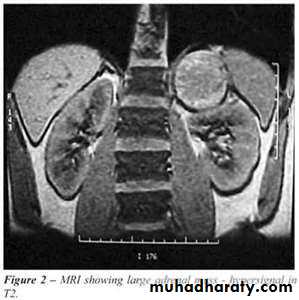

Adrenocortical carcinoma

A rare malignancy with an incidence of 1–2 cases per 1 000 000 with generally poor prognosis.A slight female predominance is observed (1.5:1).

The age distribution is bimodal with a first peak in childhood and a second between the fourth and fifth decades.

Clinical presentation

Approximately 60% of patients present with evidence of steroid hormone excess (Cushing’s syndrome).Patients with nonfunctioning tumours complain of abdominal or back pain caused by large tumours.

Diagnosis

1-measurements of DHEAS, cortisol and catecholamines to exclude a phaeochromocytoma2- dexamethasone suppression test.

3-MRI and CT are equally effective in distinguishing adrenocortical adenoma from carcinoma .